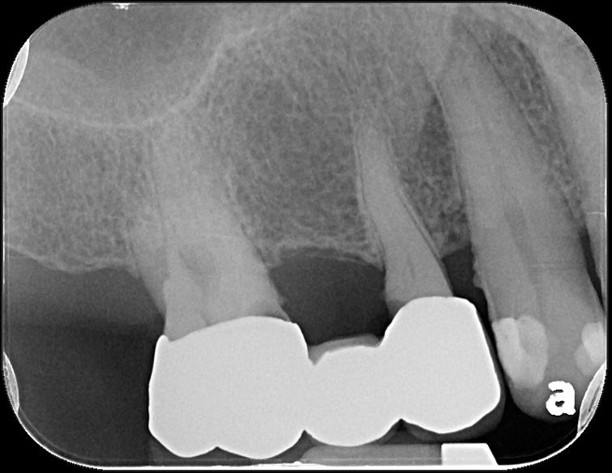

治療前,右上第一大臼齒冷熱敏感

治療前,蛀牙已侵犯至牙髓